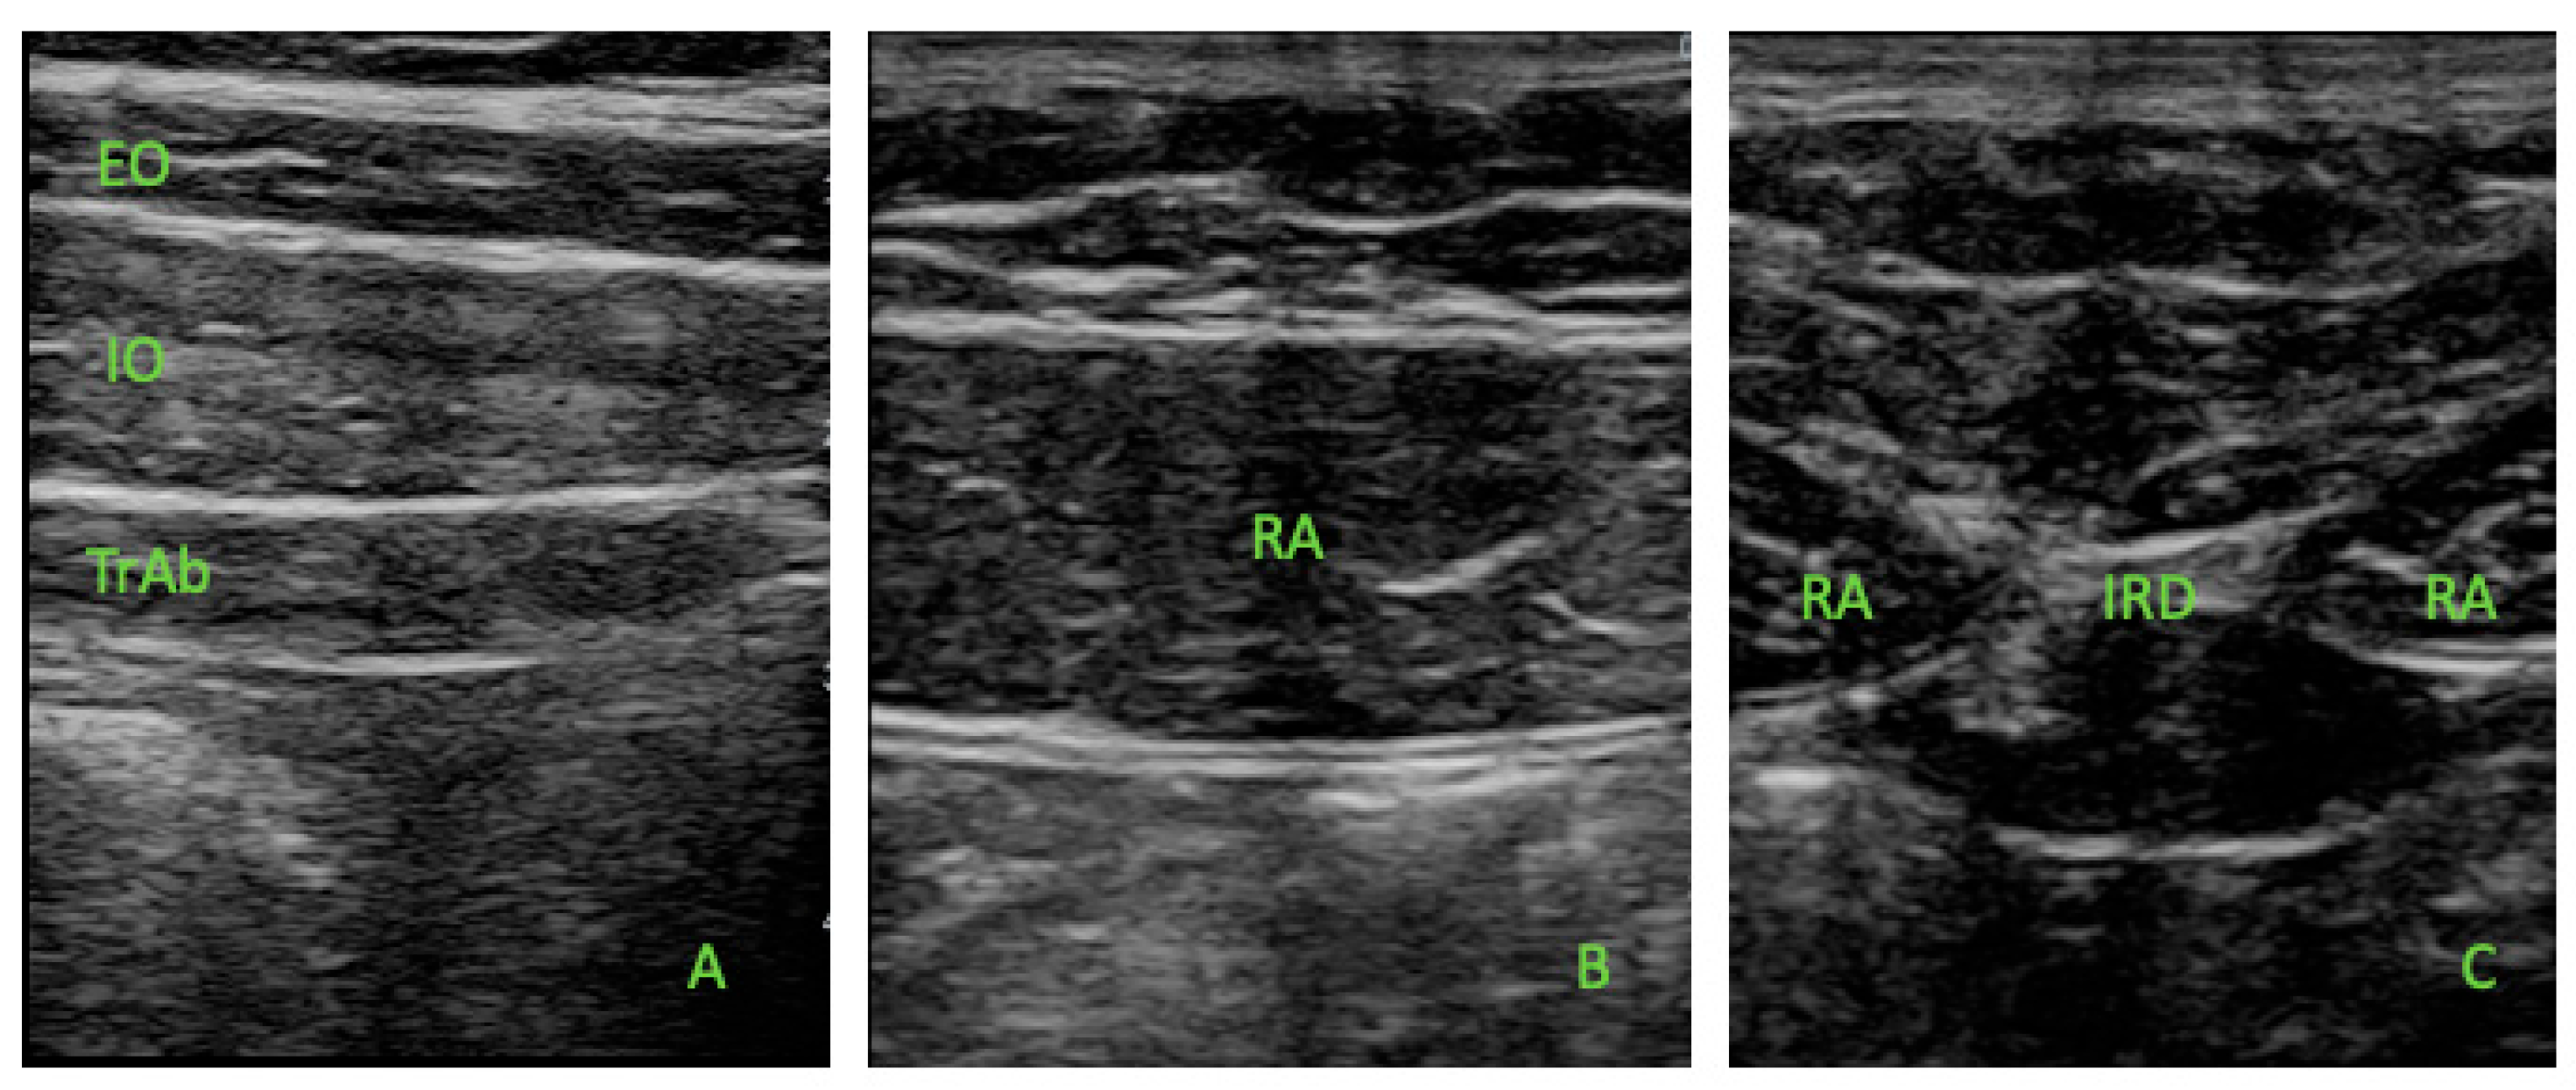

2.5. Ultrasonography Measurements